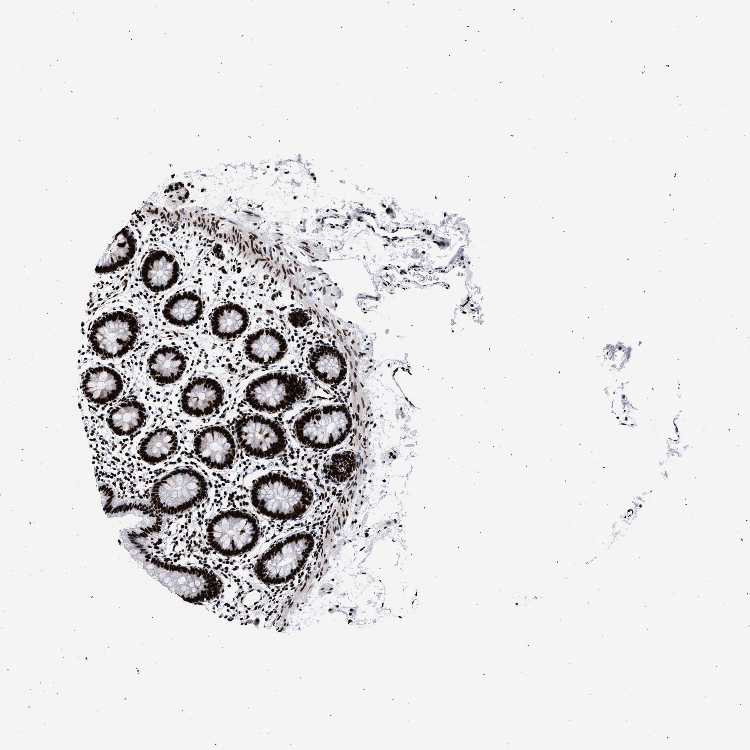

TISSUE PRIMARY DATA COLON Show tissue menu

COLON - Antibody stainingi

Antibody staining in the annotated cell types in the current human tissue is reported as not detected, low, medium, or high, based on conventional immunohistochemistry profiling in selected tissues. This score is based on the combination of the staining intensity and fraction of stained cells.

Each image is clickable and will lead to virtual microscopy that enables deeper exploration of all samples and also displays staining intensity scores, fraction scores and subcellular localization as well as patient and tissue information for each sample.

Antibody HPA001609Antibody HPA001666Antibody CAB010894

Endothelial cells MediumNot detectedMedium

Glandular cells HighHighHigh

Peripheral nerve/ganglion MediumMediumHigh